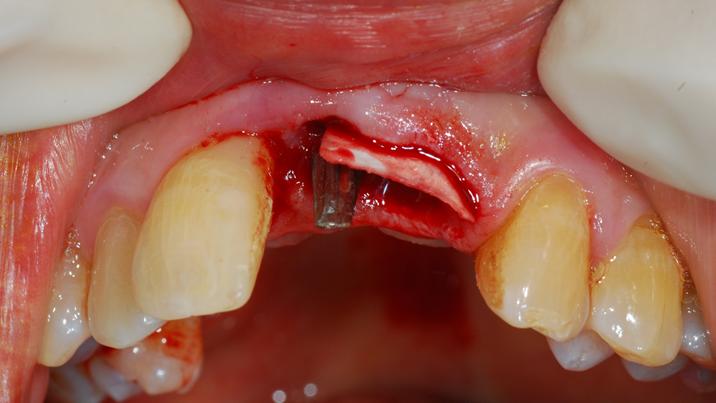

“Achieving a clean surface is the key to treating peri-implantitis!Using a titanium or NiTi brush for the decontamination process along with proper GBR can successfully restore the peri-implant environment. ”

Clinical case: Peri-implantitis treatment case using titanium or NiTi brush

- Courtesy of Dr. Dae-Hee Lee, South Korea -

Dr. Dae-Hee Lee,Maxillary Anterior,Peri-implantitis,Bone regeneration,Aesthetic zone,#21,#22,GBR,Titanium Brush Set

Titanium Brush Set